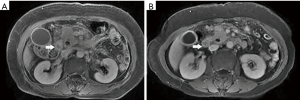

Among the AP patients, wall thickening involved duodenum (Figure 1) (27%), ascending colon (26%), stomach (20%), transverse colon (15%), jejunum (Figure 2) (14%) and ileum (6%). Dilatation of the gastrointestinal tract was seen in 8% (Figure 2, Table 2).

During treatment, 62 patients had follow up MRI examination, 16 of whom (26%) had a gastrointestinal tract abnormality on follow up examination, significantly lower than that on the initial MRI (P<0.05) (Figures 3-7). The frequencies of gastrointestinal tract abnormalities for initial and follow-up MRI examination are shown in Table 3. The difference for the frequencies of stomach, duodenum, jejunum, ileum, ascending and descending abnormal changes between before and after the treatment had statistical significance (P<0.05). There was no difference of transverse colon and bowel dilatation before and after the treatment (P≥0.05).

It was found that gastrointestinal tract wall thickness was greatly thinner after treatment (P<0.05) (Table 4).

In the follow-up MRI exam, the structure of gastrointestinal tract restored to revert in MRI, coinciding with relief of abdominal pain, recovered appetite, cessation of hematuria, amylase recovery and anal passing gas.

In this study gastrointestinal tract wall thickening was the most common finding in AP patients. Inflammatory substances can stimulate the gastrointestinal tract in patients with AP, leading to the excessive output of gastric juices and subsequent mucosal and submucosal edema (27). Some patients exhibit a three-layer structure referred to as the “target sign” (28). Tolan et al. (29) considered this pattern acute wall edema, and noted a direct correlation with inflammatory activity. In this study we found most AP patients exhibited gastrointestinal tract wall thickening, some with a stratified appearance on MRI that was similar to the “target sign” (28). After treatment, the mural stratification resolved on follow-up MRI. Our results suggested that the thickened intestinal wall in AP patients is derived from acute wall edema and can resolve soon after treatment.

We found frequent mild smooth thickening of the intestinal wall, similar to that of other non-tumorous bowel wall thickening patterns. Ramalho et al. (30) observed that the wall thickness usually ranges between 5 and 10 mm for patients with small bowel Crohn’s disease, similar to the range we noted (Table 2) in AP patients. Bowel wall thickening has been observed in bowl ischemia edema, bleeding and infection, although this thickness was unrelated to disease severity (31). Gastrointestinal tract wall thickness reduced after treatment, suggesting resolved edema after effective treatment.